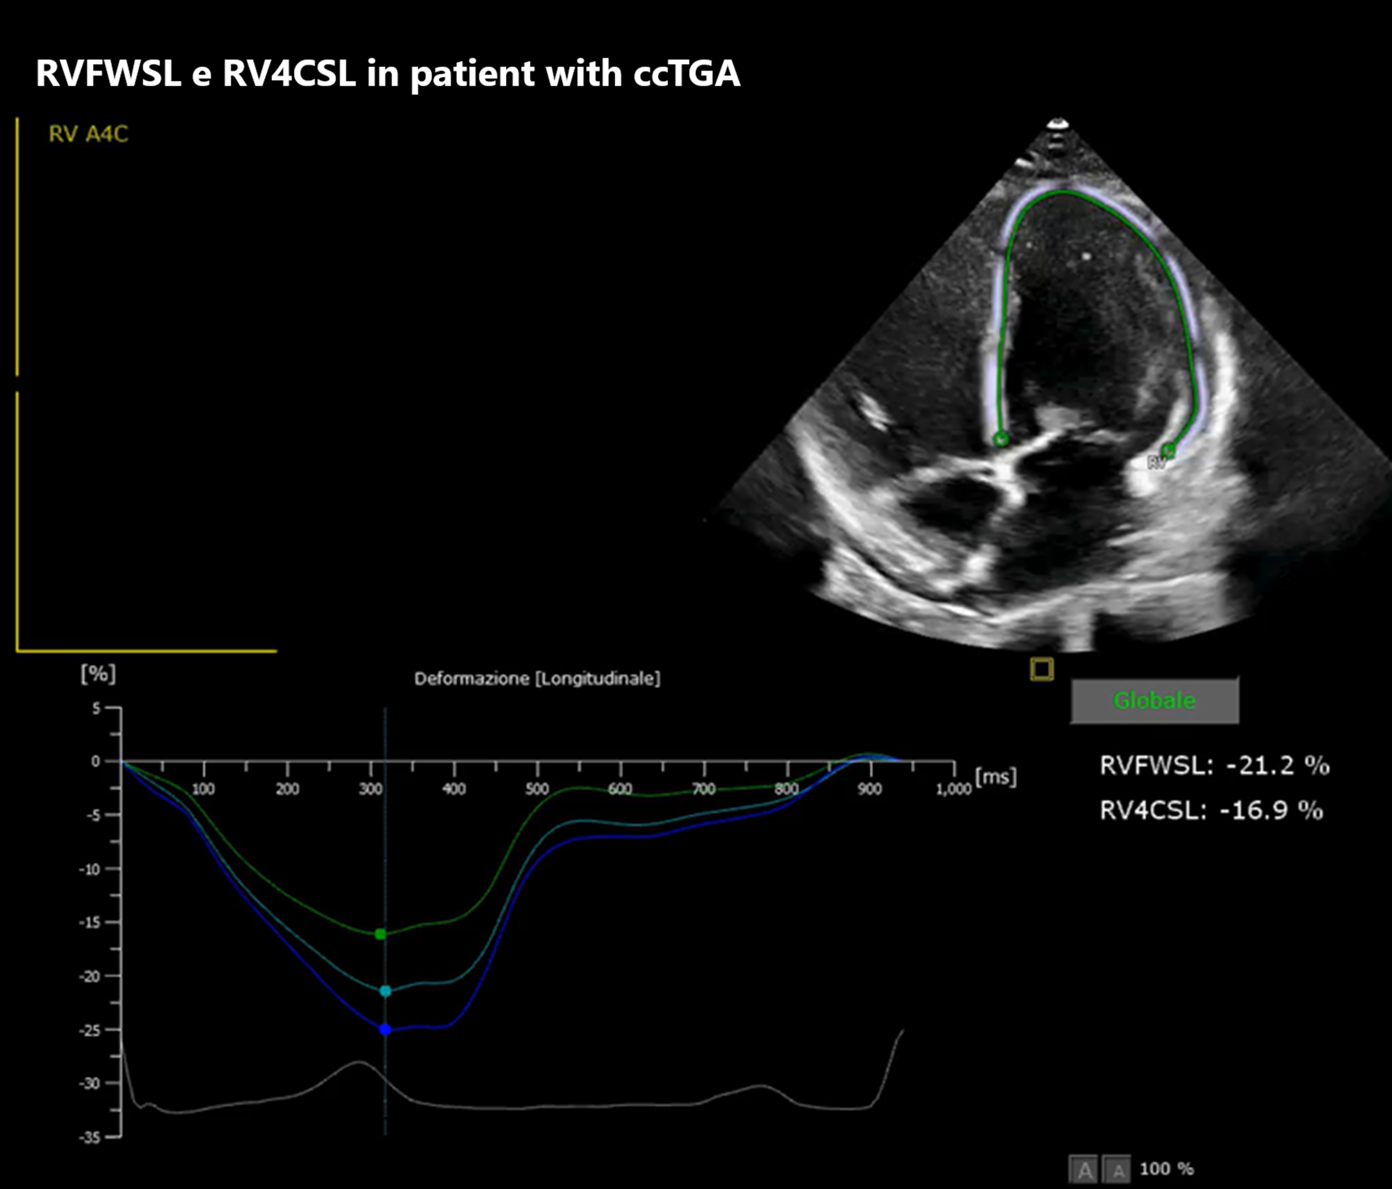

Background: The systemic right ventricle (sRV), present in patients with d-TGA after atrial switch and in congenitally corrected TGA (ccTGA), is chronically pressure-loaded, leading to ventricular remodeling and progressive dysfunction. In this setting, markers of myocardial mechanics and wall stress integrating imaging and biomarkers are useful. Aim: To evaluate the association between NT-proBNP and sRV longitudinal strain (four-chamber strain, RV4CSL, and free-wall strain, RVFWSL) and, secondarily, to describe its relationship with conventional echocardiographic indices (FAC, TAPSE, TDI S′) in a GUCH cohort with sRV in biventricular circulation (Mustard/Senning and ccTGA). Methods: Retrospective study of 20 patients followed at our Center (ARNAS Civico–Di Cristina, Pediatric Cardiology Unit). All underwent comprehensive clinical assessment with functional evaluation, laboratory testing, ECG/Holter and echocardiography; speckle-tracking strain was available in 13/20 patients. Associations were explored using linear models and Pearson correlation; NT-proBNP was also log-transformed (log10) and results were checked with Spearman as a sensitivity analysis for outliers. Results: In patients with complete echocardiographic strain and NT-proBNP data (n=13), RVFWSL was inversely associated with NT-proBNP (Pearson r=−0.555; p=0.049; Spearman ρ=−0.527; p=0.064), suggesting that reduced longitudinal deformation (less negative strain values) is accompanied by greater neurohormonal activation. RV4CSL also showed a consistent inverse association with NT-proBNP (Pearson r=−0.509; p=0.076; Spearman ρ=−0.591; p=0.033), with less negative RV4CSL values associated with higher NT-proBNP. As a complementary analysis, higher FAC was associated with higher absolute RV4CSL (r=0.624; p=0.023), whereas TAPSE and TDI S′ showed weaker but concordant associations. Conclusions: In our biventricular-circulation sRV cohort, higher NT-proBNP is associated with worse longitudinal mechanics, particularly at the free wall. Interpreted together, strain and NT-proBNP may help grade hemodynamic severity and guide follow-up; these exploratory findings require confirmation, using additional diagnostic modalities.